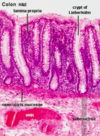

What do you see here?

- Normal colonic epithelium: irritable bowel syndrome (IBS) can present like this

- IBS is characterized by chronic, relapsing abdominal pain, bloating, and changes in bowel habits

- Despite very real symptoms, gross and microscopic evaluation is normal in most IBS patients